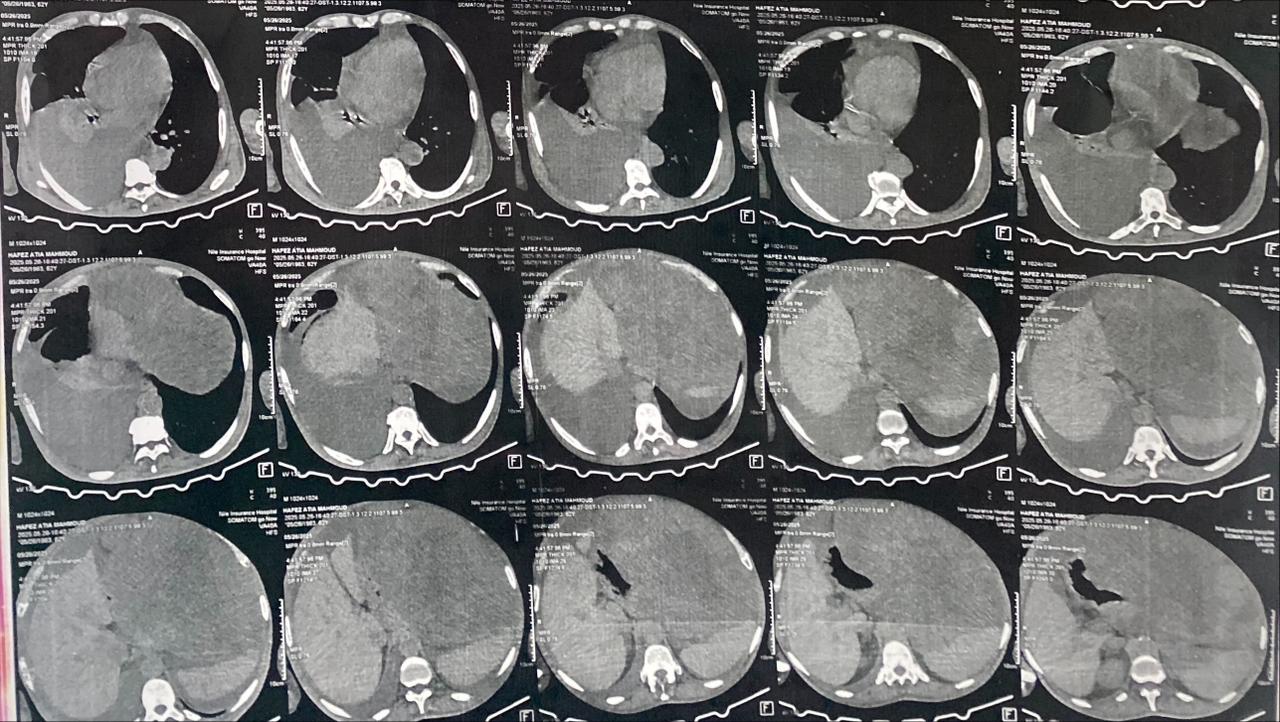

وأوضحت الوزارة أن المريض وصل إلى المستشفى وهو يعاني من ورم ضخم بلغ حجمه نحو 30×32 سم ويزن حوالي 15 كيلوجرامًا، ناشئًا من المعدة وامتد إلى عدد من الأعضاء الداخلية.

استئصال الورم

وقام الفريق الطبي بإجراء جراحة دقيقة استغرقت عدة ساعات، تم خلالها استئصال الورم مع جزء من المعدة والطحال وذيل البنكرياس ومنديل البطن، وسط متابعة دقيقة للحالة حتى تجاوز مرحلة الخطر.